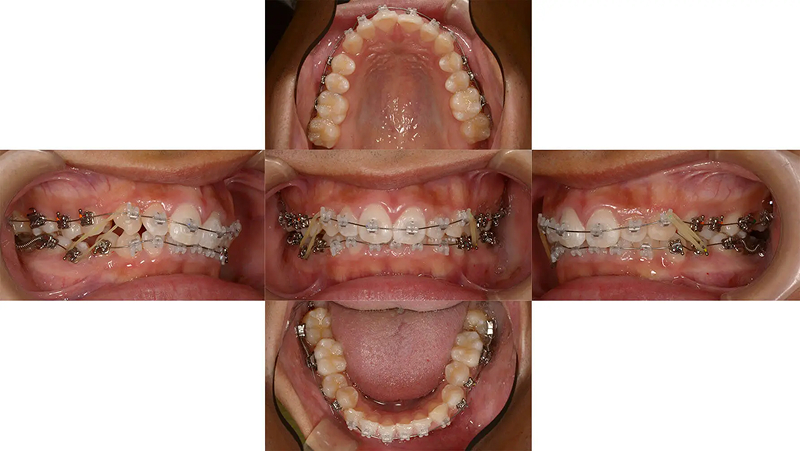

Case02前歯の凸凹を改善した症例

結婚式前に前歯の凸凹を治したいといらっしゃいました。叢生は軽度でタイムリミットは8か月でした。診査の結果、非抜歯なら十分に間に合うと診断しました。上下顎ともに少し側方拡大を行い、歯を並べました。2年後、問題なく経過しています。

初診 2017.3.23

矯正開始 2017.3.24

ファイナル 2017.10.27

治療2年後 2019.10.12

| 主訴 | 前歯の凸凹が気になる |

|---|---|

| 診断 | 両側アングル1級叢生 |

| 矯正方法 | オーバーレイアーチを併用したマルチブラケット |

| 矯正期間 | 7か月・9回 |

| 費用 | 690,000円(税別) |

| 調整料 | 月1回 5,000円(税別) |